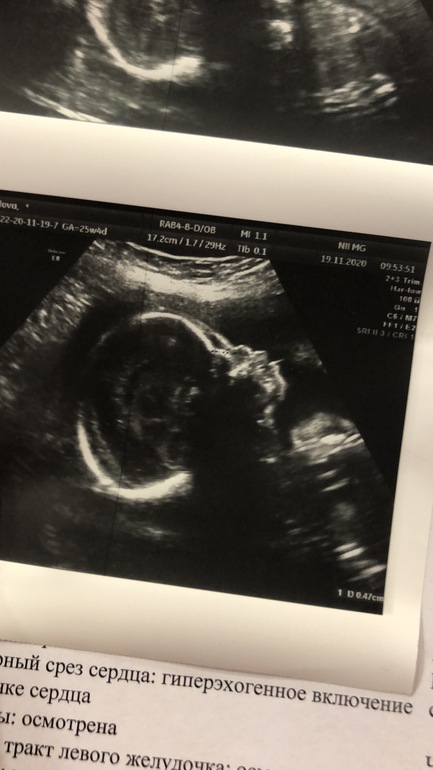

Сегодня на узи:

Носик появился.

Зубы и губы есть.

Но🤦🏻

Голова чуть больше срока.

А ноги, руки и животик меньше срока на 1,5 недели.

Но до этого у нас тоже рост отставал на 2-1 неделю.

Очень хорошо рассмотрели, сказали, что нет отклонений, но головитый и маленький будет.